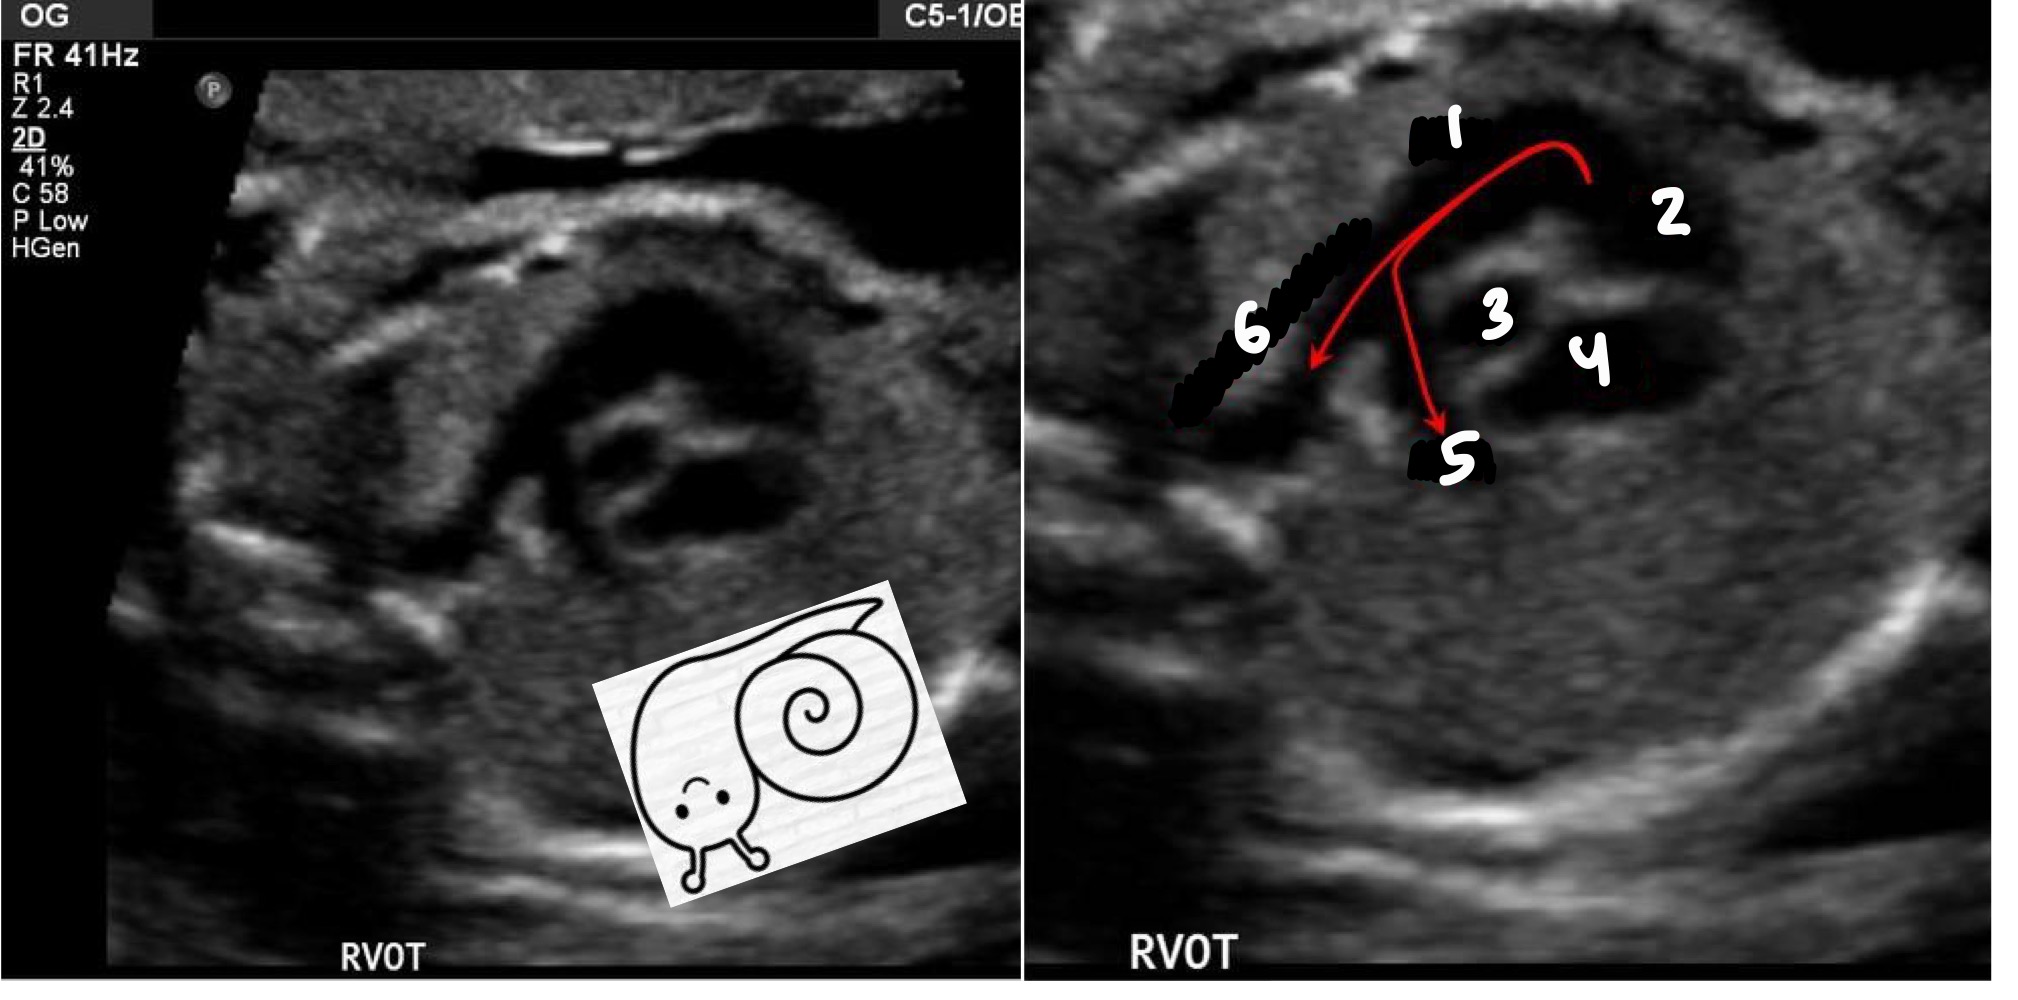

What does RVOT stand for

Right ventricular outflow tract

What vessel arises from the right ventricle

Pulmonary artery

What structures are seen after the pulmonary artery in RVOT

Ductus arteriosus and right pulmonary artery

What are common descriptors for RVOT appearance

Snail or walking man

MPA

Right ventricle

Aorta

Right atrium

Right pulmonary artery

Ductus Arteriosus